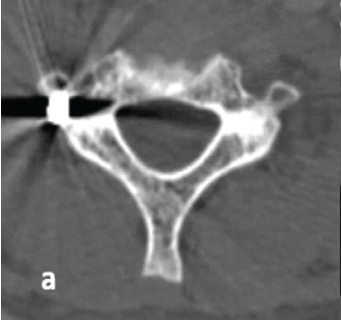

The Computed Tomography-based Morphometry of Thoracolumbar Junction (T11–L2) in Western Indian Population: Implications for Transpedicular Screw Fixation

Sandeep Kumar Yadav , Ramakishan Chaudhary , Kishore Parihar , Rajesh Kumar Rajnish , Anil Meena , Rahul Meena

………………………………p.335-340